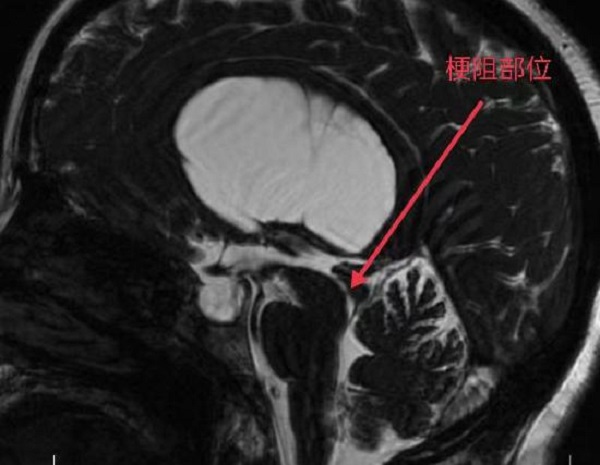

隨著神經(jīng)內(nèi)鏡設(shè)備的不斷更新和微侵襲技術(shù)的快速發(fā)展,腦室鏡下第三腦室底造瘺術(shù)(ETV)優(yōu)勢(shì)凸顯, 已經(jīng)成為了梗阻性腦積水的首選。近日,二一五醫(yī)院神經(jīng)重癥監(jiān)護(hù)室在成功開展腦積水之腦室鏡下三腦室底造瘺術(shù)后,原有...